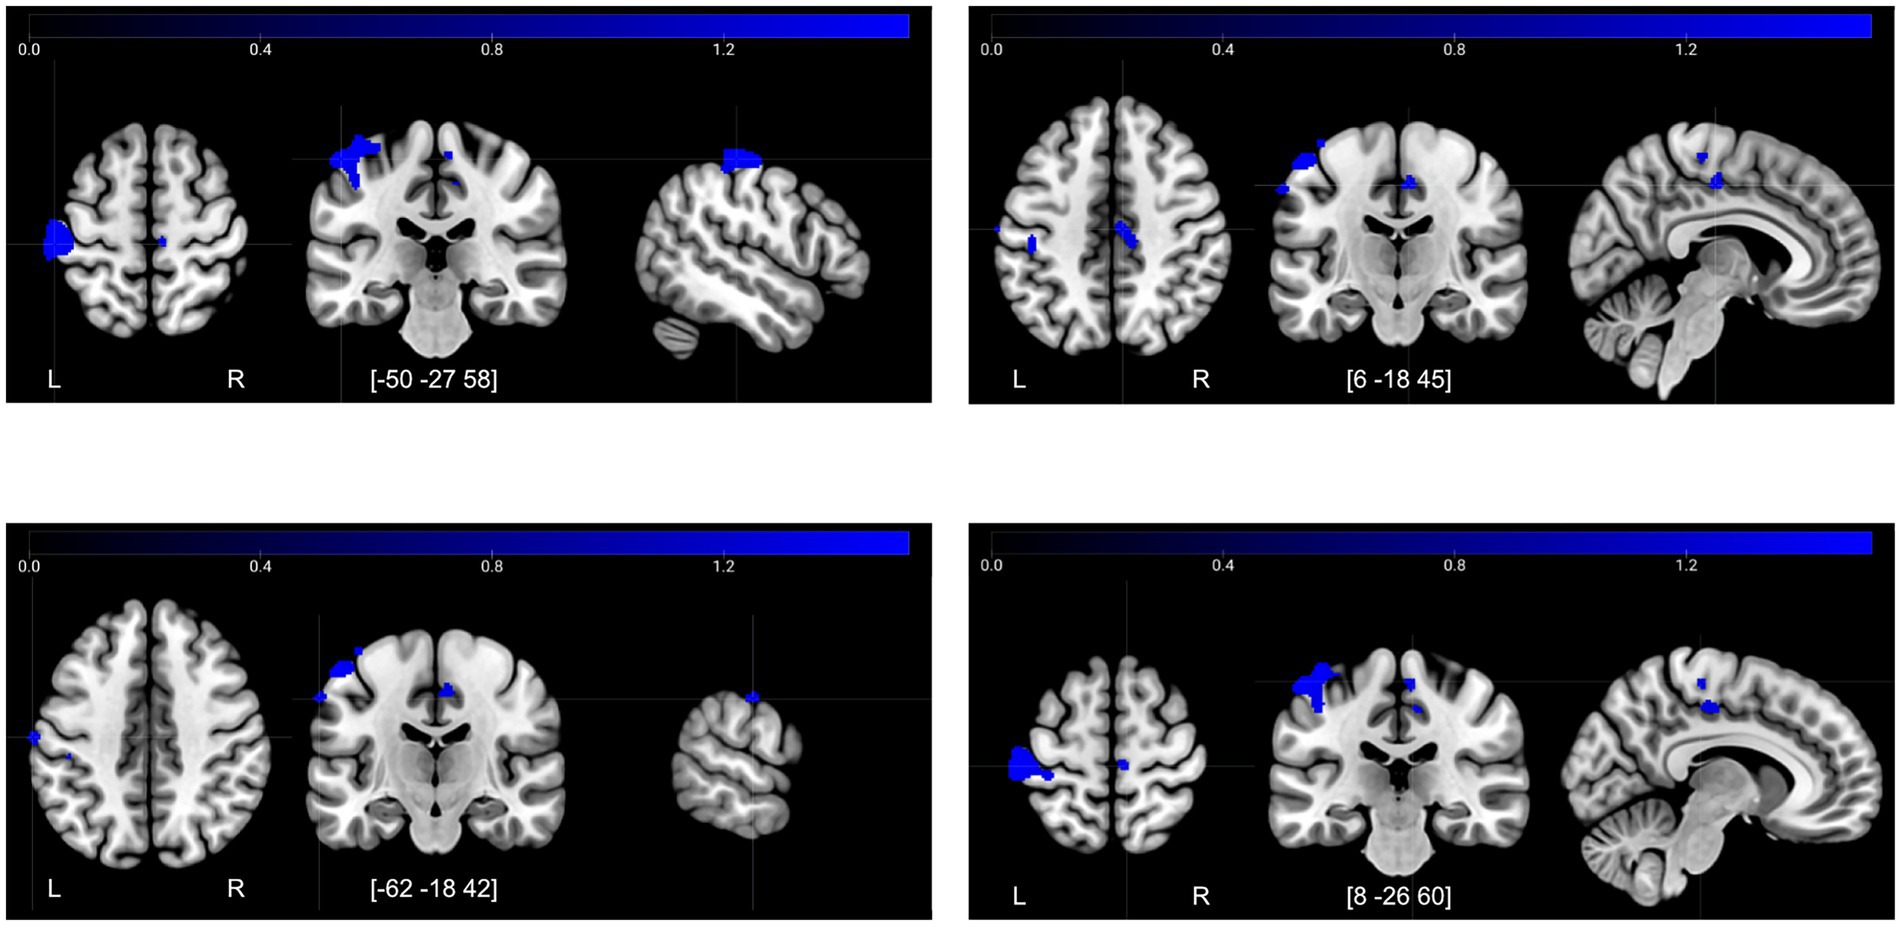

| Decreases T2→T3, encoding−control | |||||

| Postcentral gyrus | −50 | −27 | 58 | 1,535 | 1836 |

| Posterior cingulate gyrus | 6 | −18 | 45 | 130 | 1,619 |

| Postcentral gyrus | −62 | −18 | 42 | 47 | 1,605 |

| Precentral gyrus | 8 | −26 | 60 | 37 | 1,601 |

Significant increases and decreases in brain activity after the control period and intervention period (TFCE FWE-corrected p < 0.05).

Peak = voxel coordinates (MNI-space) of peak activity in the cluster, kE = cluster size, TFCE = critical threshold value to yield a FWE rate of 5%.

Figure 5

![Four panels showing brain MRI scans with highlighted blue areas. Each panel displays axial, coronal, and sagittal views. Blue regions indicate specific brain adeactivation or functionality at different coordinates: top left [-50 -27 58], top right [6 -18 45], bottom left [-62 -18 42], and bottom right [8 -26 60]. A color bar at the top indicates intensity levels from zero to 1.2. Letters L and R denote left and right sides of the brain.](https://www.frontiersin.org/files/Articles/1679873/xml-images/fnagi-17-1679873-g005.webp)

Increases in activity at T2 compared to T1 for the contrast retrieval–control. Illustrated regions significant at a TFCE FWE-corrected threshold of p < 0.05.

The decreases in activity after the intervention for Encoding–Control (Figure 6) were located in the sensory cortex—in the hand area and also in the face area. Interestingly, there was a cluster of decreased activity in the mid/posterior cingulate cortex, which is a region associated with attention allocation (Small et al., 2003) and response selection (Leech and Sharp, 2014). Based on this latter finding, we also included the posterior cingulate cortex as a ROI in the functional connectivity analysis.